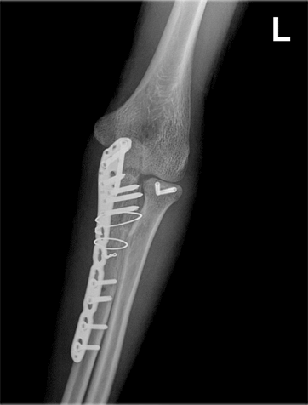

팔꿈치관절 골절의 종류 및 치료

과상부 골절, 요골두 골절, 척골 골절

척골 요골두 골절